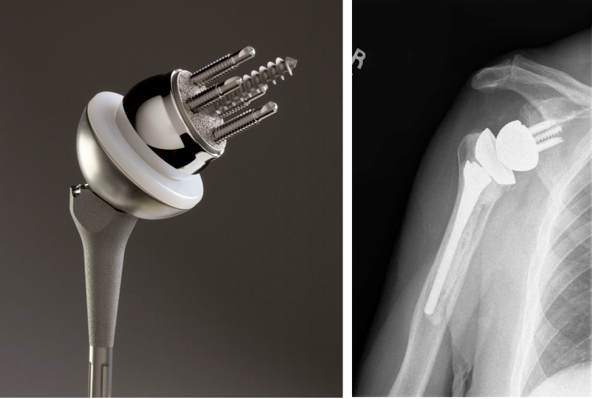

위의 사진과 같이 기존의 인공관절은 humerus 의 골두를 제거하고 glenoid 모습과 비슷하게 작동하는 원리로 인공관절이 되었으나 최근에는 humerus head 의 medialization 효과와 deltoid muscle lever arm의 증가로 더 효과가 있는 reverse shoulder arthroplasty 가 많이 시행되고 있습니다. 1990년대부터 수술을 시작했으니 30년 정도 지난 수술법입니다.

쉽게 생각하면 Convex 와 Concave가 반대로 된 구조라고 생각하면 됩니다. 회전의 중심(Center Of Motion)이 좀더 아래와 안쪽에 위치한 생역학적 장점을 갖고 있습니다.

대신 반대로 상완골의 움직이면서 glenoid의 하방부를 notching 하는 부작용이 쉽게 생길 수 있습니다. 이를 scapular notching 이라고 합니다. base plate를 좀더 lateral inferior 하게 삽입하면 이를 예방할 수 있습니다. 또한 glenosphere 크기를 늘리고 lateral offset을 늘리는 방법도 있습니다.